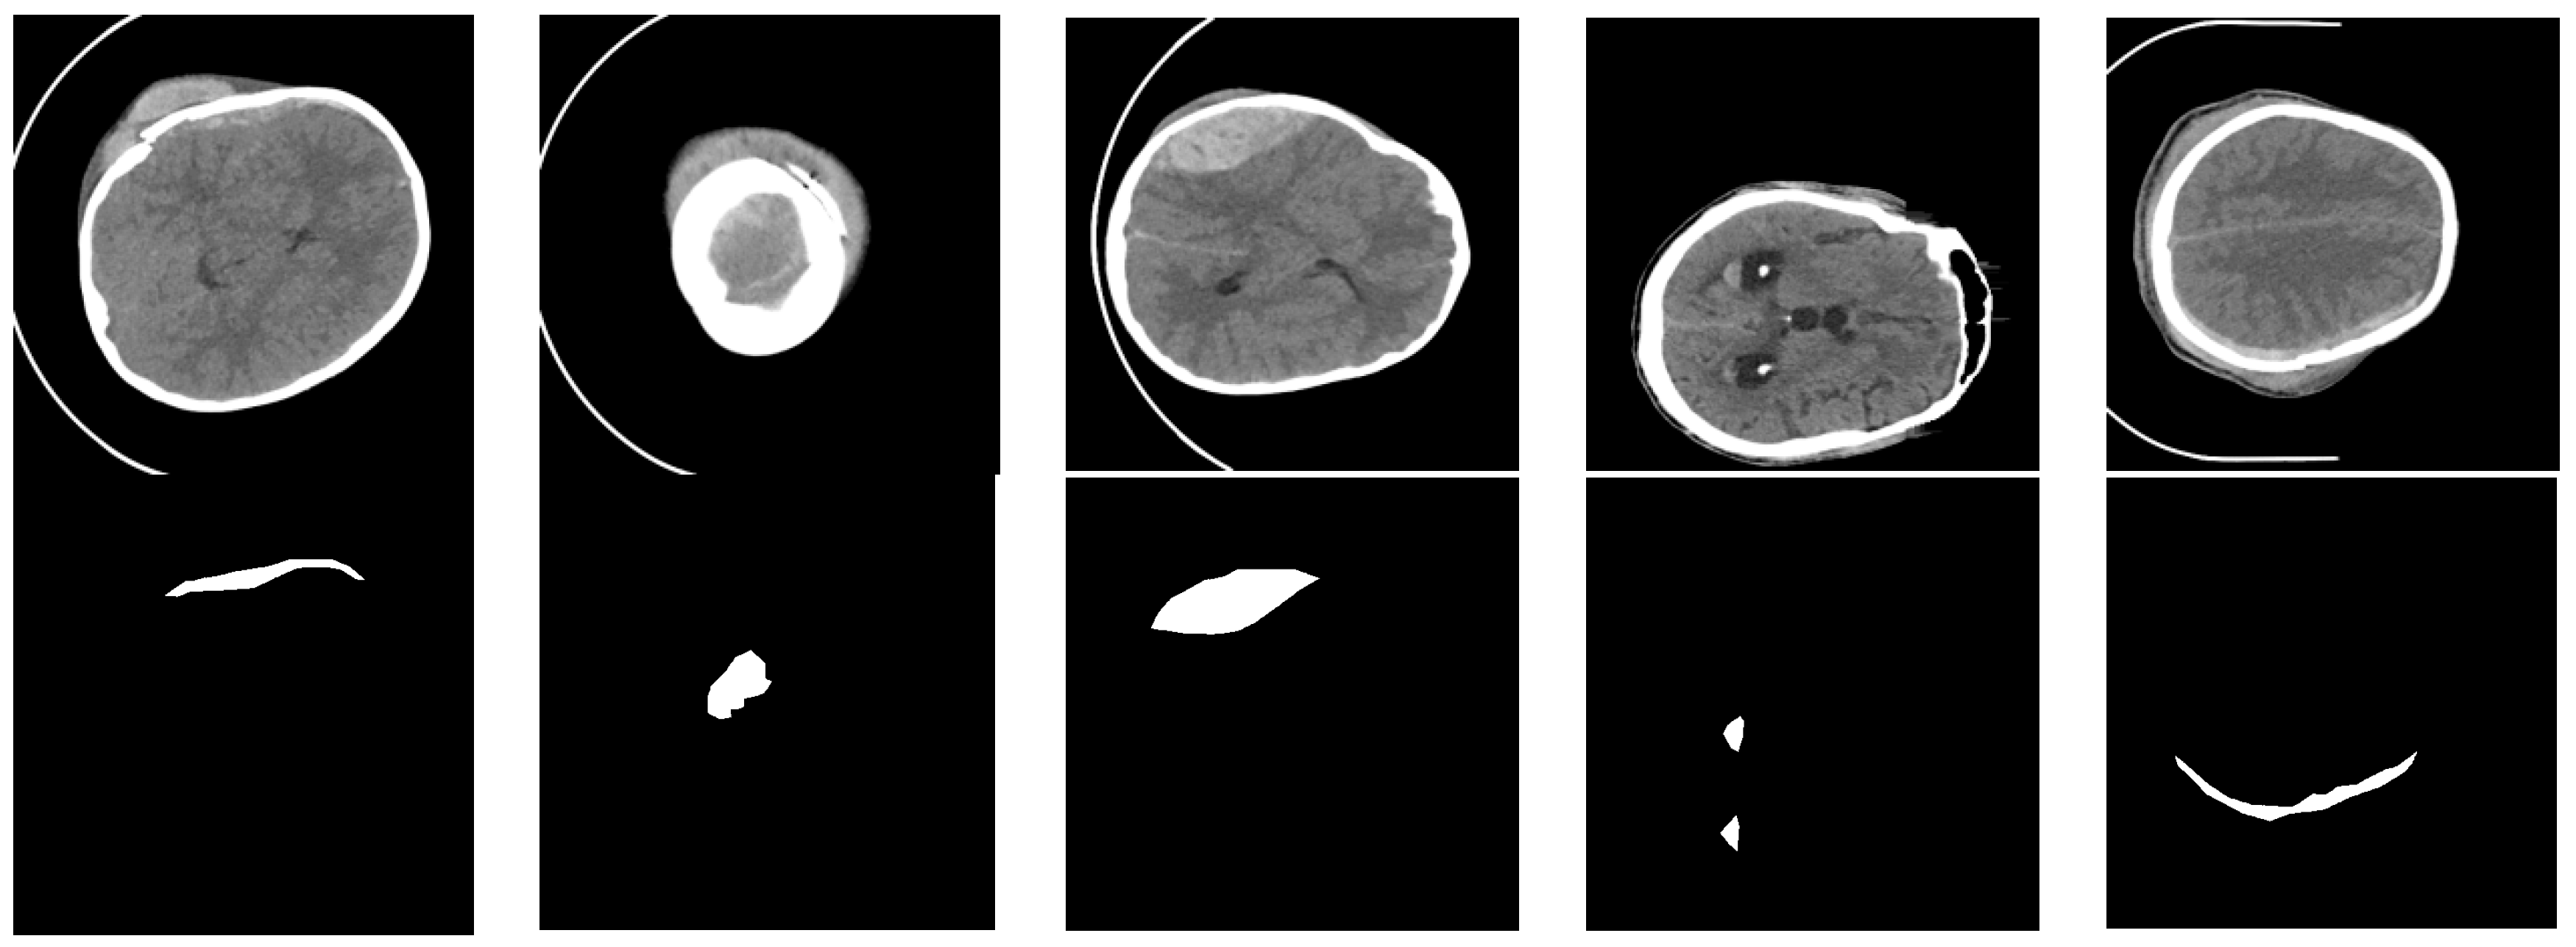

3.1. Image Preprocessing

4.1. Dataset